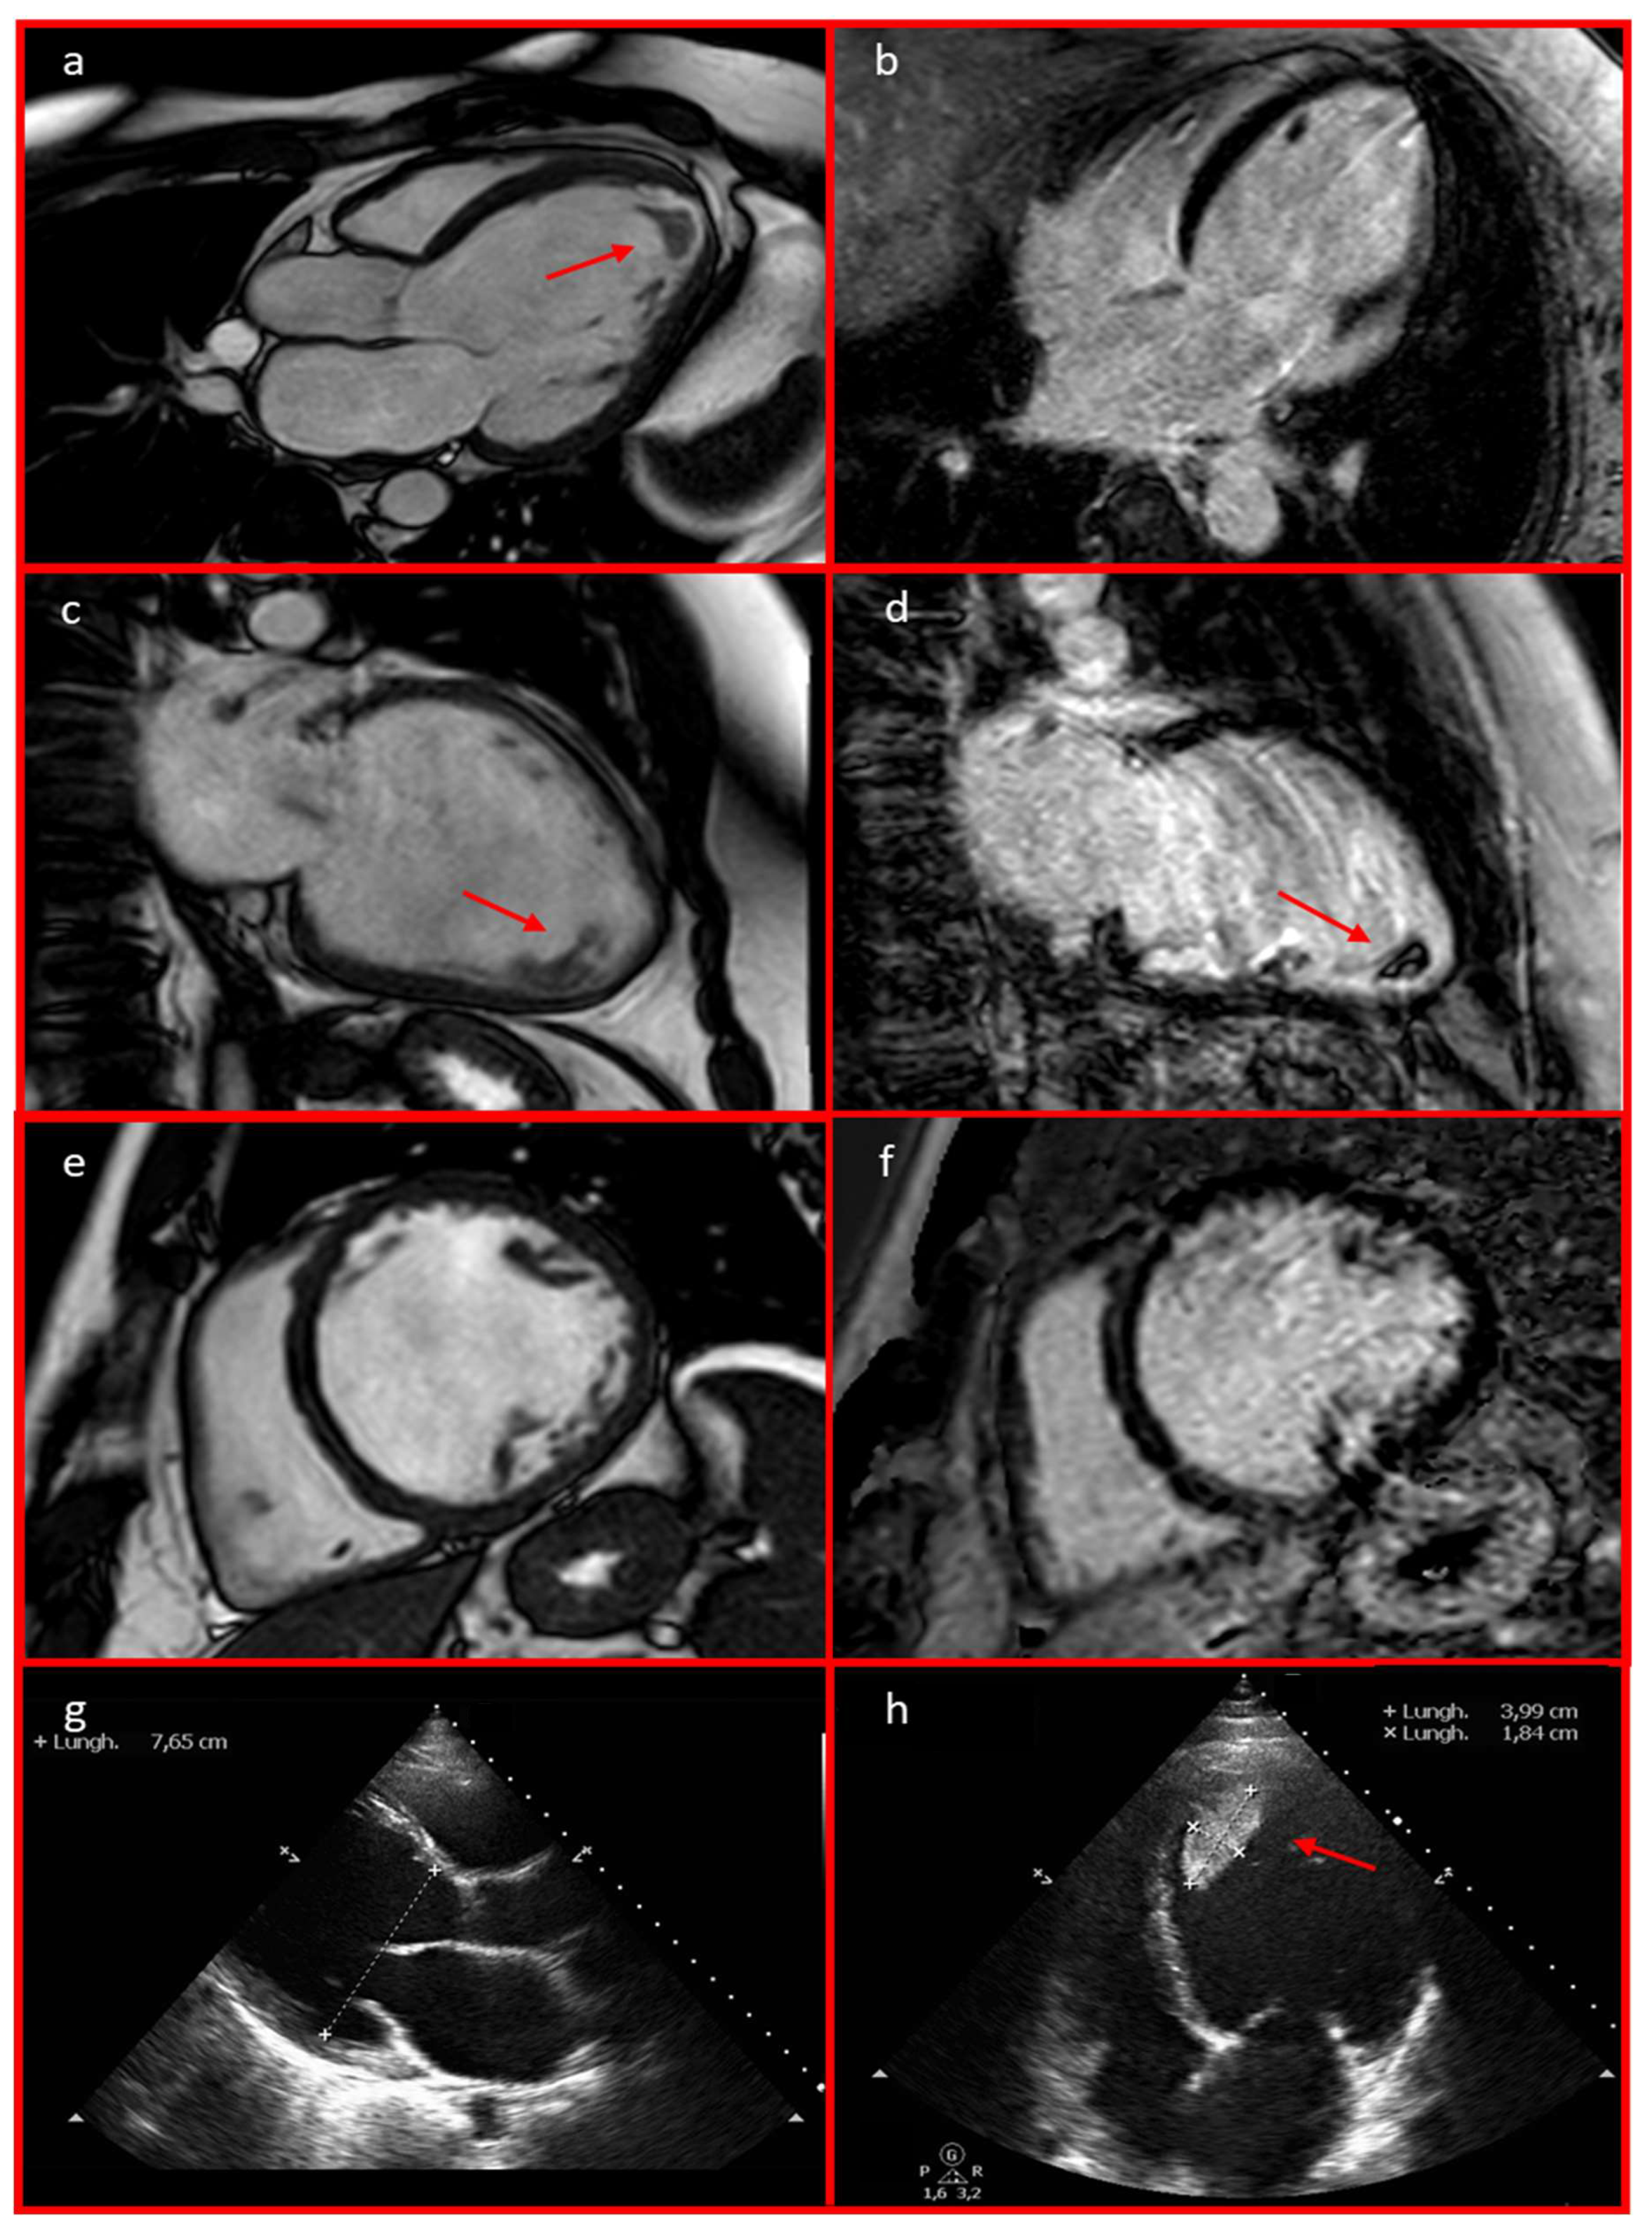

2. Detailed Case Description